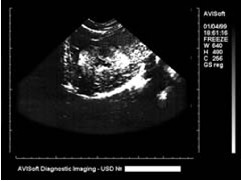

Укажите, для какого заболевания характерны изменения на сонограмме

-цирроз печени

-острый гепатит

-жировая дистрофия печени

-киста печени

-гемангиома

*гепатоцеллюлярный рак

-метастазы

Перечислите основные симптомы на представленной сонограмме

-округлая форма образования

*неправильная форма образования

-четкие контуры образования

*неоднородная структура образования

-однородная структура образования

*нечеткие контуры образования